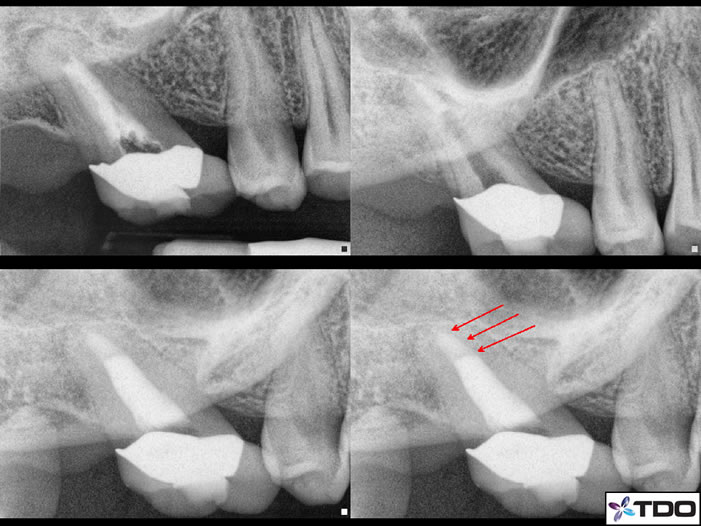

Figure 5: This case was just finished by Dr. Sherman. The pre-op shows wide open apices with tooth #8 having received inadequate original endodontic treatment. Tooth #9 is necrotic with incomplete apical formation. MTA is packed in the apical 4mm and a bonded fiber post over the top of the MTA.

Figure 6: I completed this case a couple years ago. the pre-op with over instrumented and over filled RCT in the upper left. The upper right is with all materials removed. The lower left is with MTA in the apical section. And the lower right is the completed case with bonded post/composite seal.

Figure 8: Root end resorption on a necrotic case. Following proper canal disinfection I packed MTA in the apical 4mm (red arrows). I then placed gutta percha in the rest of the canal and sealed coronally with composite.